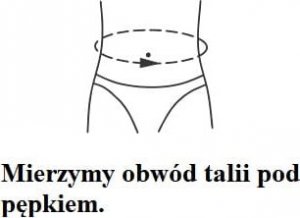

Przy doborze rozmiaru prosimy zmierzyć obwód w pasie zaraz pod pępkiem.

- S 66 - 85 cm

- M 80 - 100 cm

- L 84 - 108 cm

- XL 90 - 110 cm